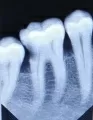

Собираюсь лечить 5-й и 6-й зуб сверху. Врач говорит, что в 5-ке придётся убрать нерв. Зуб не беспокоит, на холодное горячее не реагирует, такая же ситуация с нижним 7-ым зубом. У верхнего зуба мудрости на снимке глубокий кариес.

Скажите, какая вероятность при лечении, что пульпа не вскроется? Возможно ли сохранить оба эти зуба с питанием? Стоит ли удалять зуб мудрости или можно повременить?

В верхнем пятом зубе кариозный процесс распространился глубоко. Можно попытаться сохранить пульпу, работая на низких оборотах.

В нижнем седьмом и шестом зубах имеется процесс на контактной поверхности. Зубы необходимо пролечить, пока процесс не распространился глубже. Седьмой зуб можно попытаться вылечить без удаления нерва, а вот шестой лучше перелечить, так как каналы запломбированы не до верхушки корня, что может привести в дальнейшем к воспалительному процессу в области верхушки корней.